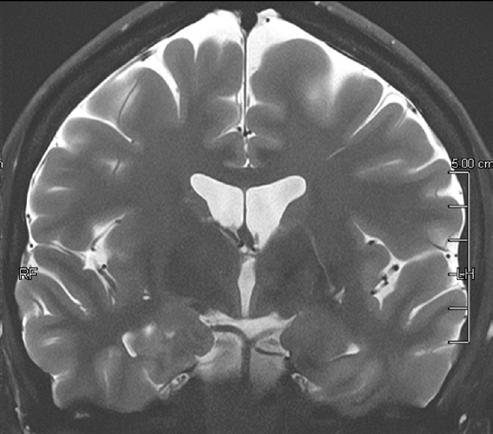

3D FLAIR with DLR. 3D FLAIR Original image. 100s, 0.5x0.5x0.6mm reconstructed

In particular DLR has an important clinical impact in anatomical regions that require a very high resolution, for example parts of the hippocampus and the claustrum.

“The DLR brings a spatial resolution that I have never seen before in neurologic imaging. I recently pointed out a brain area, for example the claustrum, that is almost invisible on standard MRI images even with very high resolution or high field devices. However, thanks

to the DLR we could highlight this kind of brain anatomy. So, indeed, there is a considerable advantage to using this technique.” Prof. Dousset said.

Prof. Tourdias worked at 7T to visualise extremely fine structures of the hippocampus while at Stanford. With DLR, he can now do this task with a 3T. “When we compared the images we realized that by pushing the 3T machine and processing with DLR that we were able to achieve a similar result to what we could achieve with 7T. I think this is the main surprise of the technology.” he said.

Original Coronal T2w image.

Coronal T2w image with DLR.